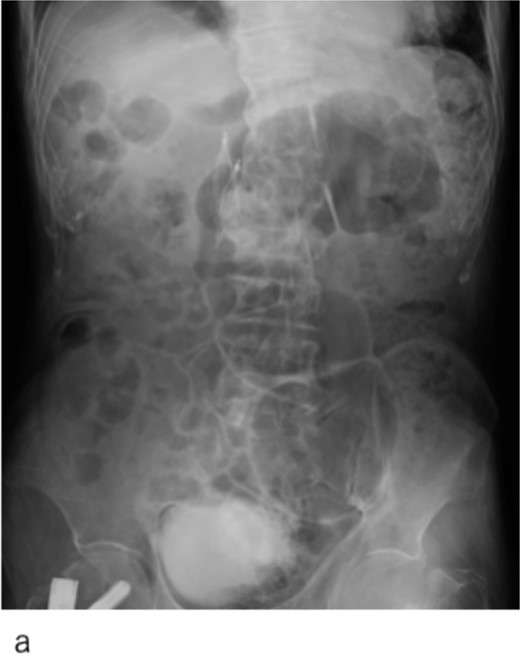

Abdominal X-ray image after the surgery. Two inferior vena cava filters are placed.